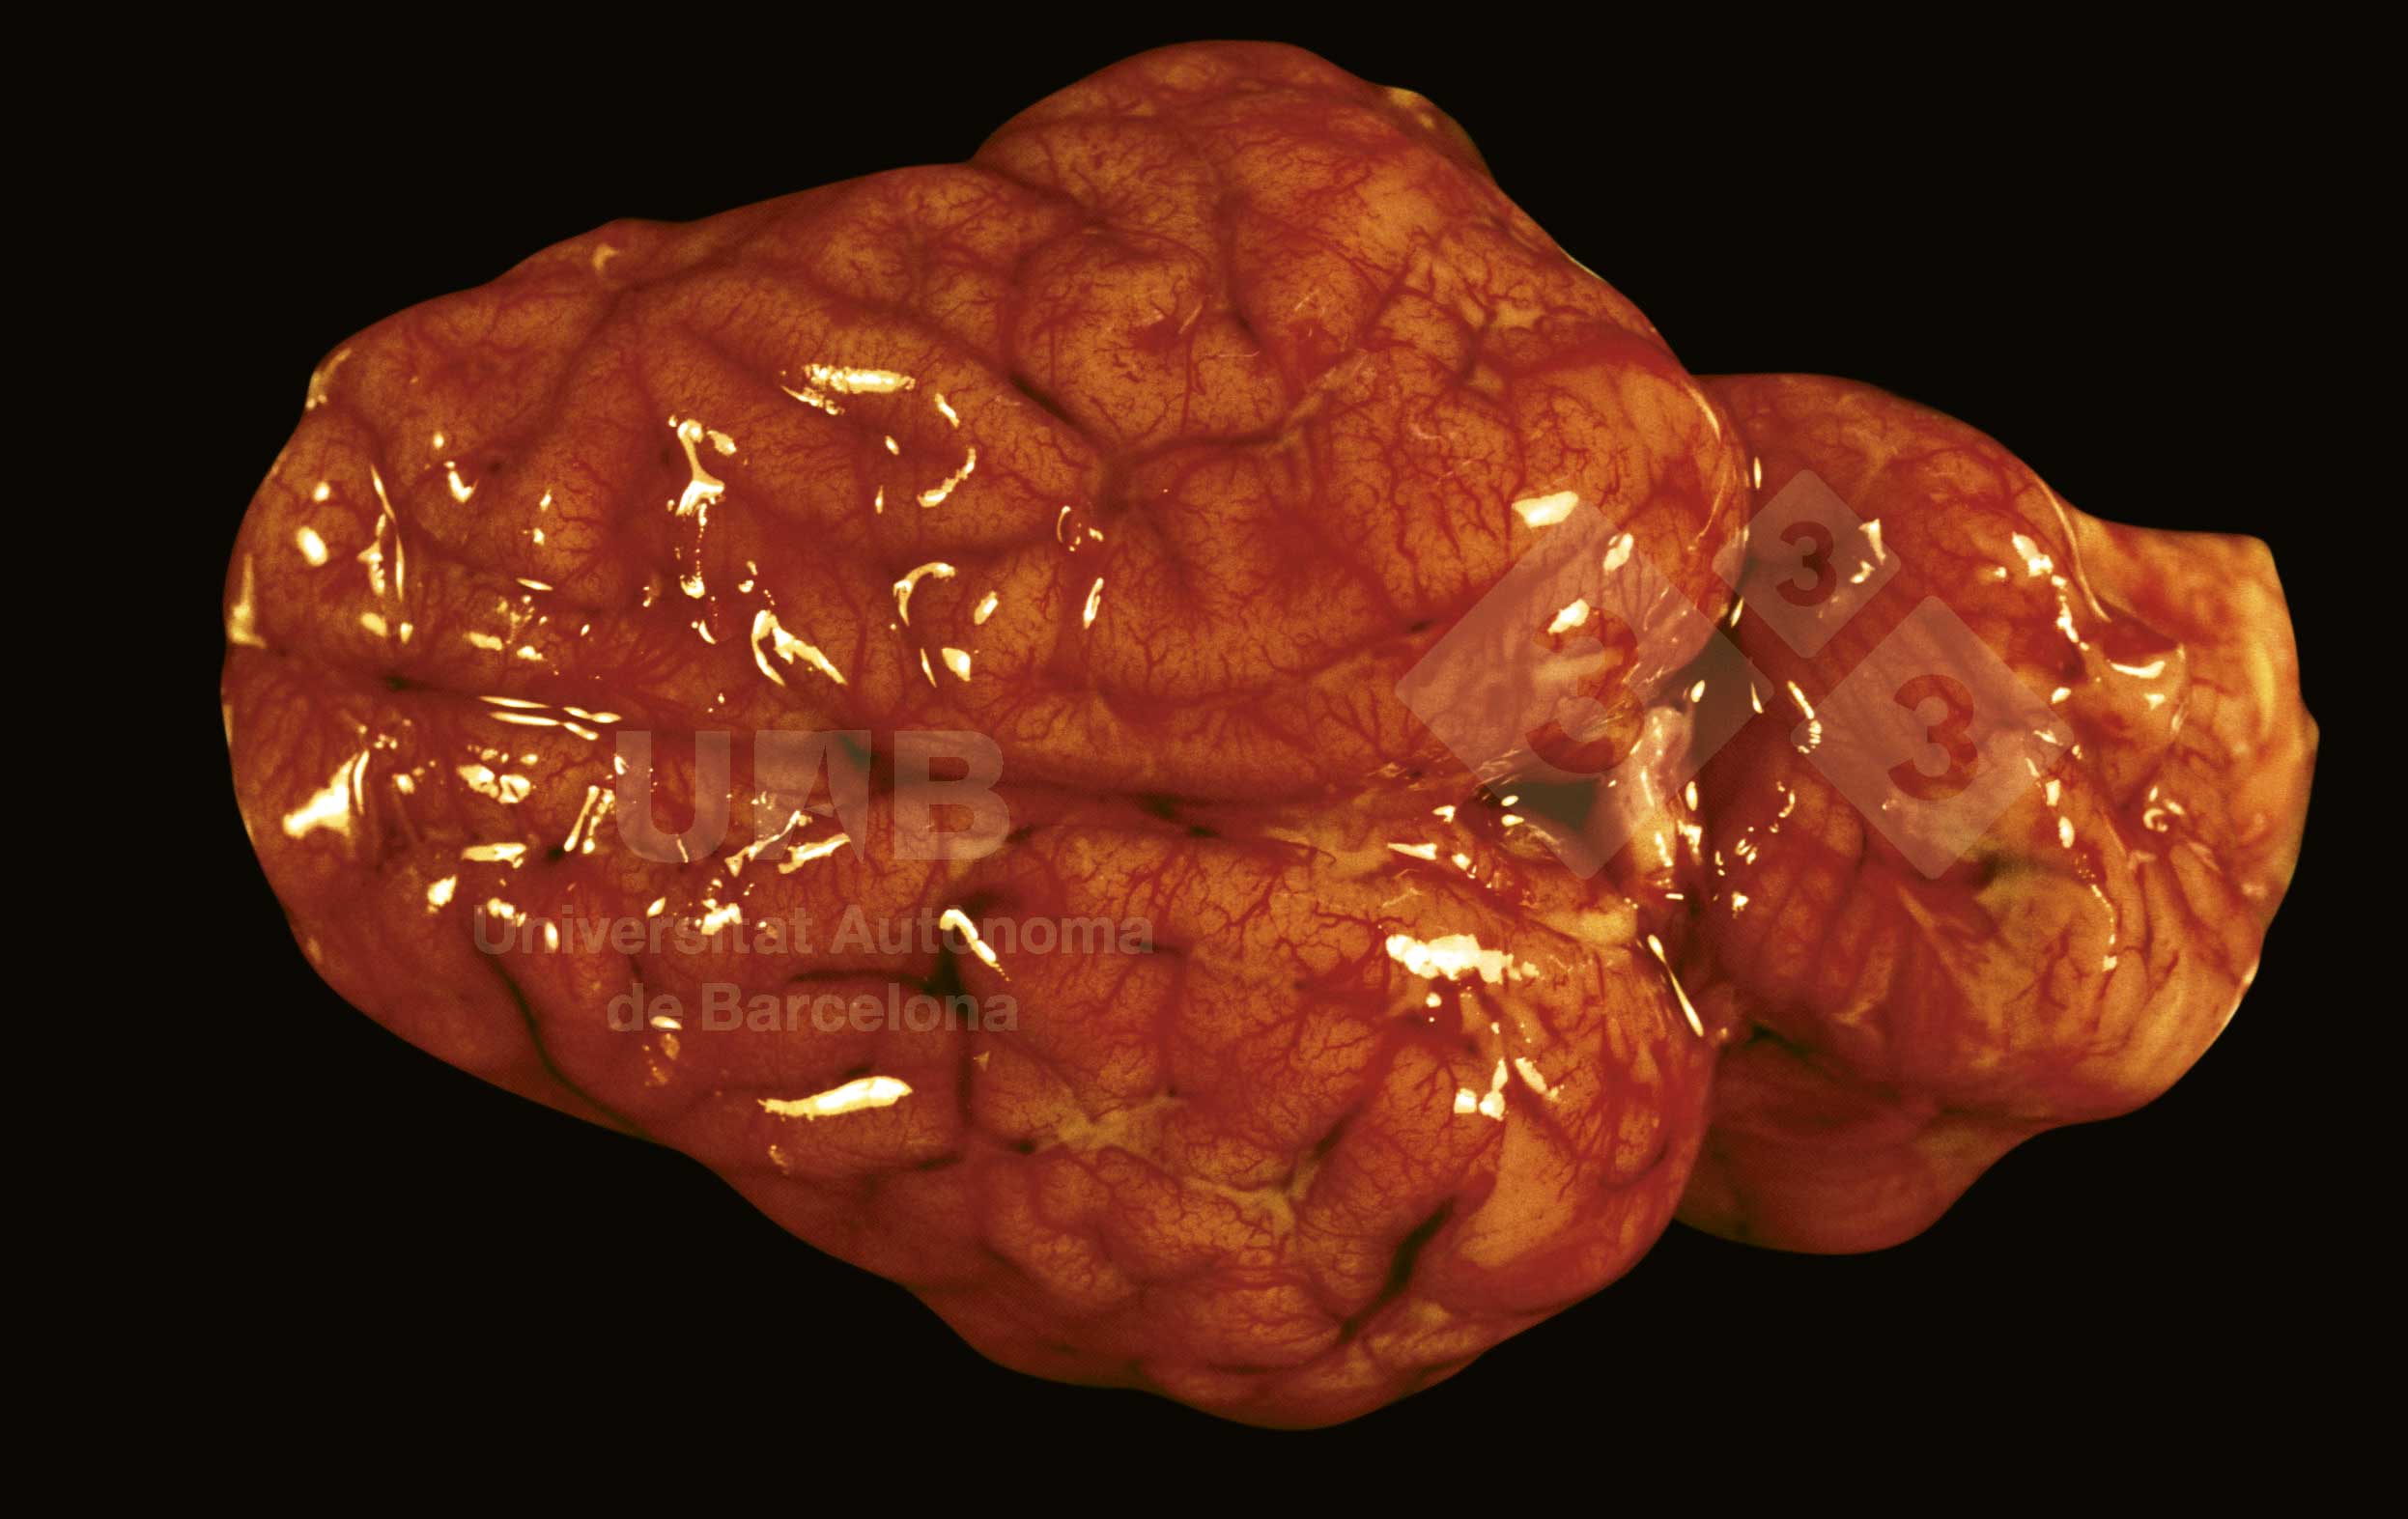

Quand les méninges sont inflammés on observe une sévère congestion. Parfois, comme dans ce cas, il apparait un exsudat fibrineux multifocal dans les replis. L'étiologie de la méningite est une infection bactérienne par Streptococcus suis, Haemophilus parasuis et Escherichia coli, entre autres.